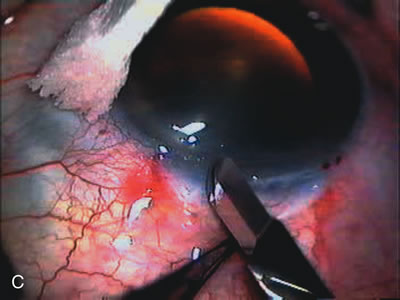

Fig. 7. Phacotrabeculectomy adjacent to a failed filter in cataractous eye. The ability to combine small-incision cataract extraction with trabeculectomy all through the same incision adjacent to the failed filter allows the surgeon to work in a familiar superior area. Avoiding incisions into the existing bleb decreases conjunctival buttonholes, hypotony, operating room time, and subconjunctival bleeding. A. Appearance of failed bleb with exposure of superior temporal quadrant gained with a corneal traction suture. B. Prepare a limbus-based conjunctival flap and a scleral flap. C. This bleb is at high risk to fail again justifying the need for MMC, 0.2 mg/cc applied on a pledget for 4 minutes. D. Insert the keratome and perform phacotrabeculectomy in the usual fashion.

The inflammation associated with lens extraction at any site usually causes complete failure of a marginal functioning bleb. In addition, pressure reduction by medical means is usually minimal in these recalcitrant cases, and combined surgery is indicated. In the past, these cases were approached with large-incision ECCE, clear corneal cataract incision, and bleb revision. Drawbacks included those mentioned earlier for large incision clear corneal cataract extraction, and bleb revision is often associated with conjunctival buttonholes, wound leaks, subconjunctival hematoma, destruction of friable sclera, and associated hypotony. With the advent of modern-day cataract surgery, a phacotrabeculectomy is often possible adjacent to the failed filter (Fig. 7). The ability to combine cataract extraction with implant and filtration surgery all through the same small incision has greatly improved outcomes for patients with marginal preoperative filters. There are several other viable options in this case. If the surgeon elects to remove the cataract through a temporal clear corneal incision, the bleb may be revised or a new adjacent filter fashioned. As mentioned earlier, revising a failed filter is technically challenging. If the surgeon believes it is not feasible to revise the filter or fashion a new one, a glaucoma drainage implant is a reasonable option combined with temporal lens extraction.172